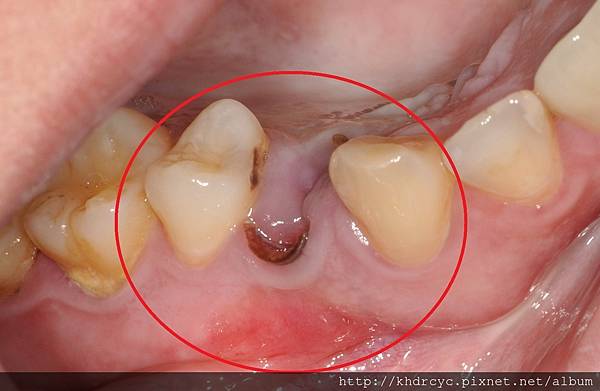

楠梓H小姐牙齒爛掉已久有相同問題

一直不敢看牙醫 鼓起勇氣請欣美牙醫幫忙

欣美牙醫幫忙在植牙手術中同時補骨

楠梓H小姐非常有信心的預約下一顆植牙

了解植牙手術中同時補骨

恢復牙肉與牙齒的外觀與厚度

完全感覺不出植牙跟一般牙齒的差別